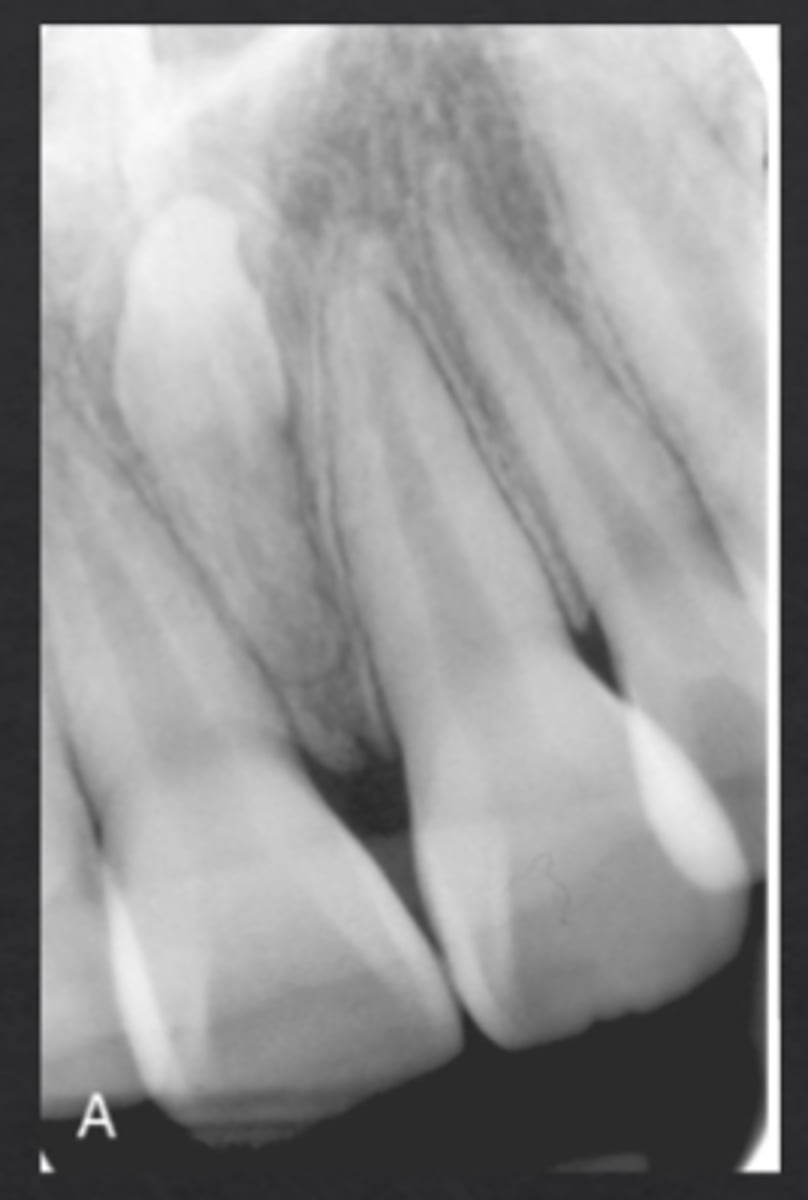

What is dilaceration?

Sharp bend or curvature of a tooth root

Why is dilaceration clinically important?

Can complicate extractions and RCT

What is fusion?

Two tooth buds fuse to form one tooth

How many teeth are present in fusion cases?

One fewer than normal

What is gemination?

One tooth bud attempts to divide into two crowns

How many teeth are present in gemination cases?

Normal number of teeth